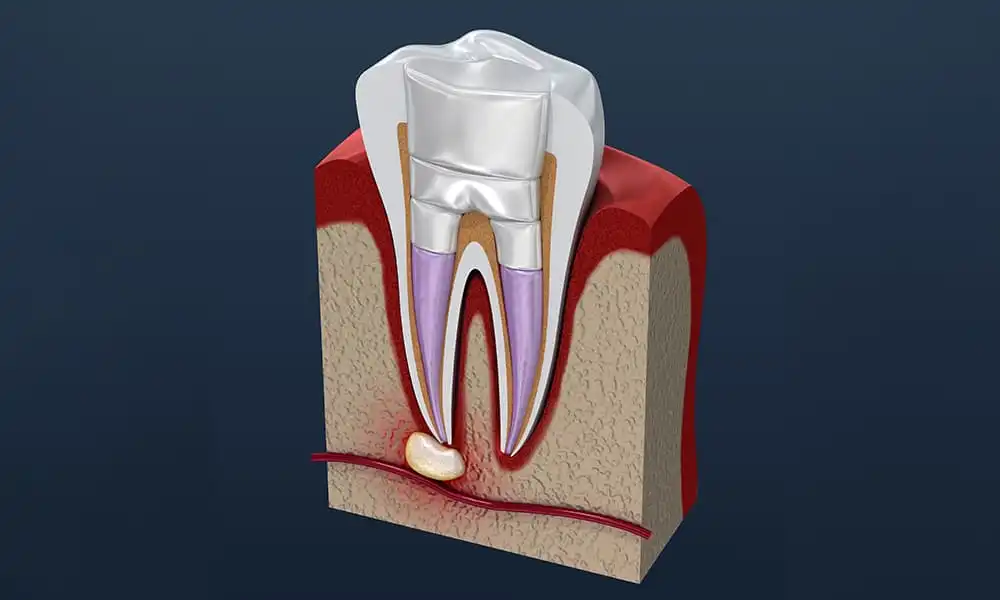

「根の先に膿が溜まっていて、もう抜くしかないと言われた」

通常の根管治療だけでは治癒が難しいケースに対し、当院では外科的なアプローチ(口腔外科的処置)を併用することで、抜歯を回避します。

歯根端切除術(しこんたんせつじょじゅつ)

根の先に溜まった膿の袋(根尖病変)が大きく、通常の治療では治りきらない場合、歯ぐき側からアプローチして根の先を数ミリ切除し、病巣を直接取り除く手術です。